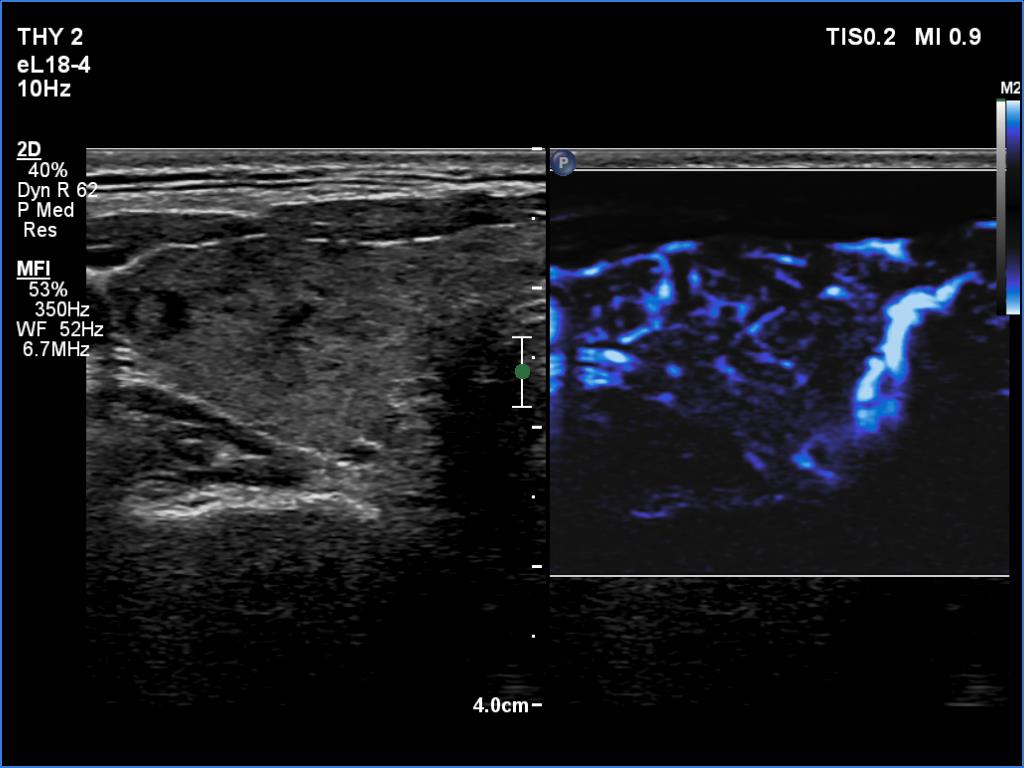

Left lobe, longitudinal scan

Left lobe, microflow imaging